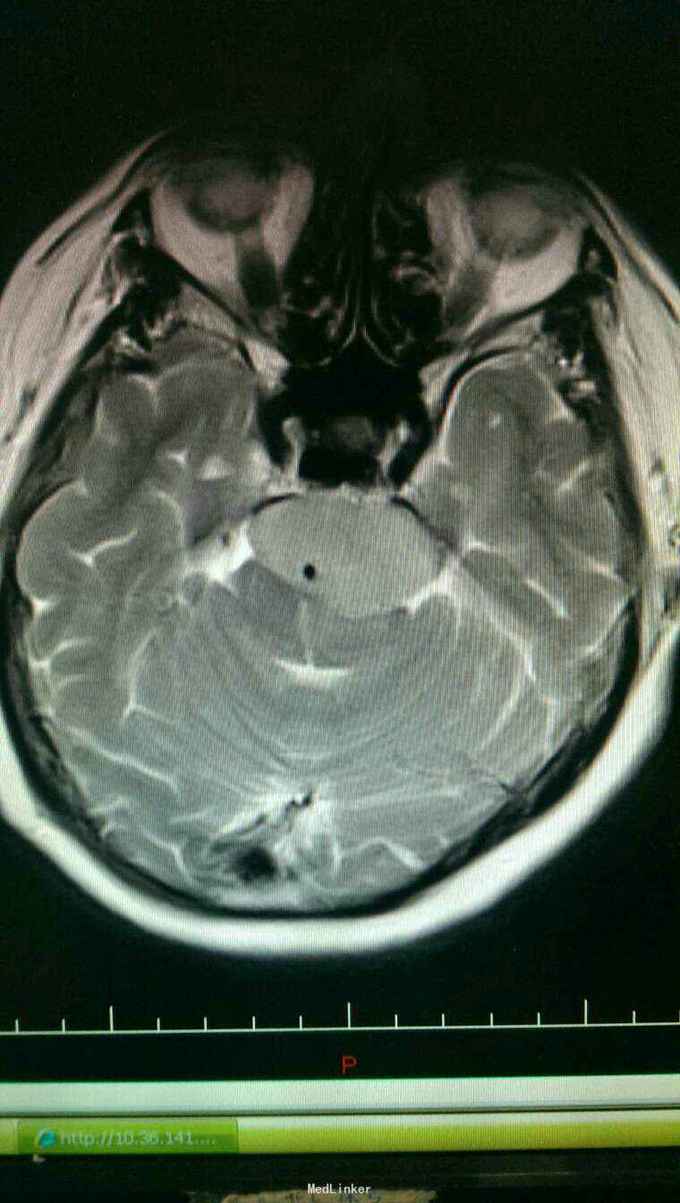

入院诊断:岩斜区脑膜瘤。完善术前准备,于全麻下行右侧颞下入路,岩斜区肿瘤切除,术中保留拉贝静脉,剪开小脑幕,近全切除肿瘤。

患者术后病情稳定,岩斜区位于颞骨岩部背面与枕骨斜坡部的岩斜裂汇合处,从岩骨尖至颈静脉孔。内侧至斜坡中线,外侧至第Ⅴ、Ⅶ和Ⅷ脑神经,上缘为鞍背,下缘为颈静脉孔水平;下方为枕骨大孔区。岩斜区脑膜瘤由于位置深,毗邻重要解剖结构,很难实现肿瘤全切除,且有较高的术后致残率,一直是神经外科手术的治疗难点。颅内脑膜瘤约0.3%~1.0%起源于岩斜区,是岩斜区最常见病变。它向上可侵犯岩骨尖、小脑幕、Meckel腔、鞍旁和海绵窦;向下侵犯内听道和颈静脉孔;向内侧达脑干和椎-基底动脉。当肿瘤很大时,可包绕同侧Ⅲ~Ⅺ脑神经。患者临床可表现头痛、复杂的脑神经麻痹、共济失调等症状,严重者表现为偏瘫、认知功能障碍。岩斜区脑膜瘤多数表现良性过程,目前,仍以手术切除为首选治疗方式。 岩斜区脑膜瘤手术技术非常关键,需要熟悉岩斜区解剖关系并有丰富的显微操作经验。在术前放置腰穿引流,或术中甘露醇应用可明显降低脑组织压力,减少牵拉造成的副损伤。提前对脑膜瘤基底的处理可有效避免肿瘤持续出血造成的蛛网膜界面消失。肿瘤的生长将神经、血管拉伸或包绕,尤其是复发的肿瘤,会破坏蛛网膜界面,侵犯脑干软脑膜。手术时应仔细分辨和保护。肿瘤囊壁与神经、血管外膜和脑干粘连,不应勉强分离,以保护下方结构。 待术后平稳复查头Ct。